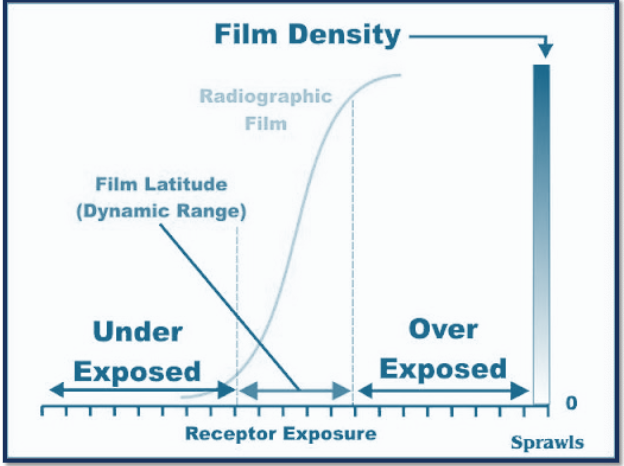

dynamic range

number of shades an imaging system can produce

dynamic range is identified by…

bit depth of each picel

increase in display of greater shades in grey has ______ dynamic range and _____ contrast resoluition

greater; better

as exposure increase _____ increases

densities

body

useful range of densities

toe

underexposed

shoulder

overexposed

digital exposure lattitude is

wide

in digital exposure you can underexposure by%

50%

in digital exposure you can overexpose by:

400%